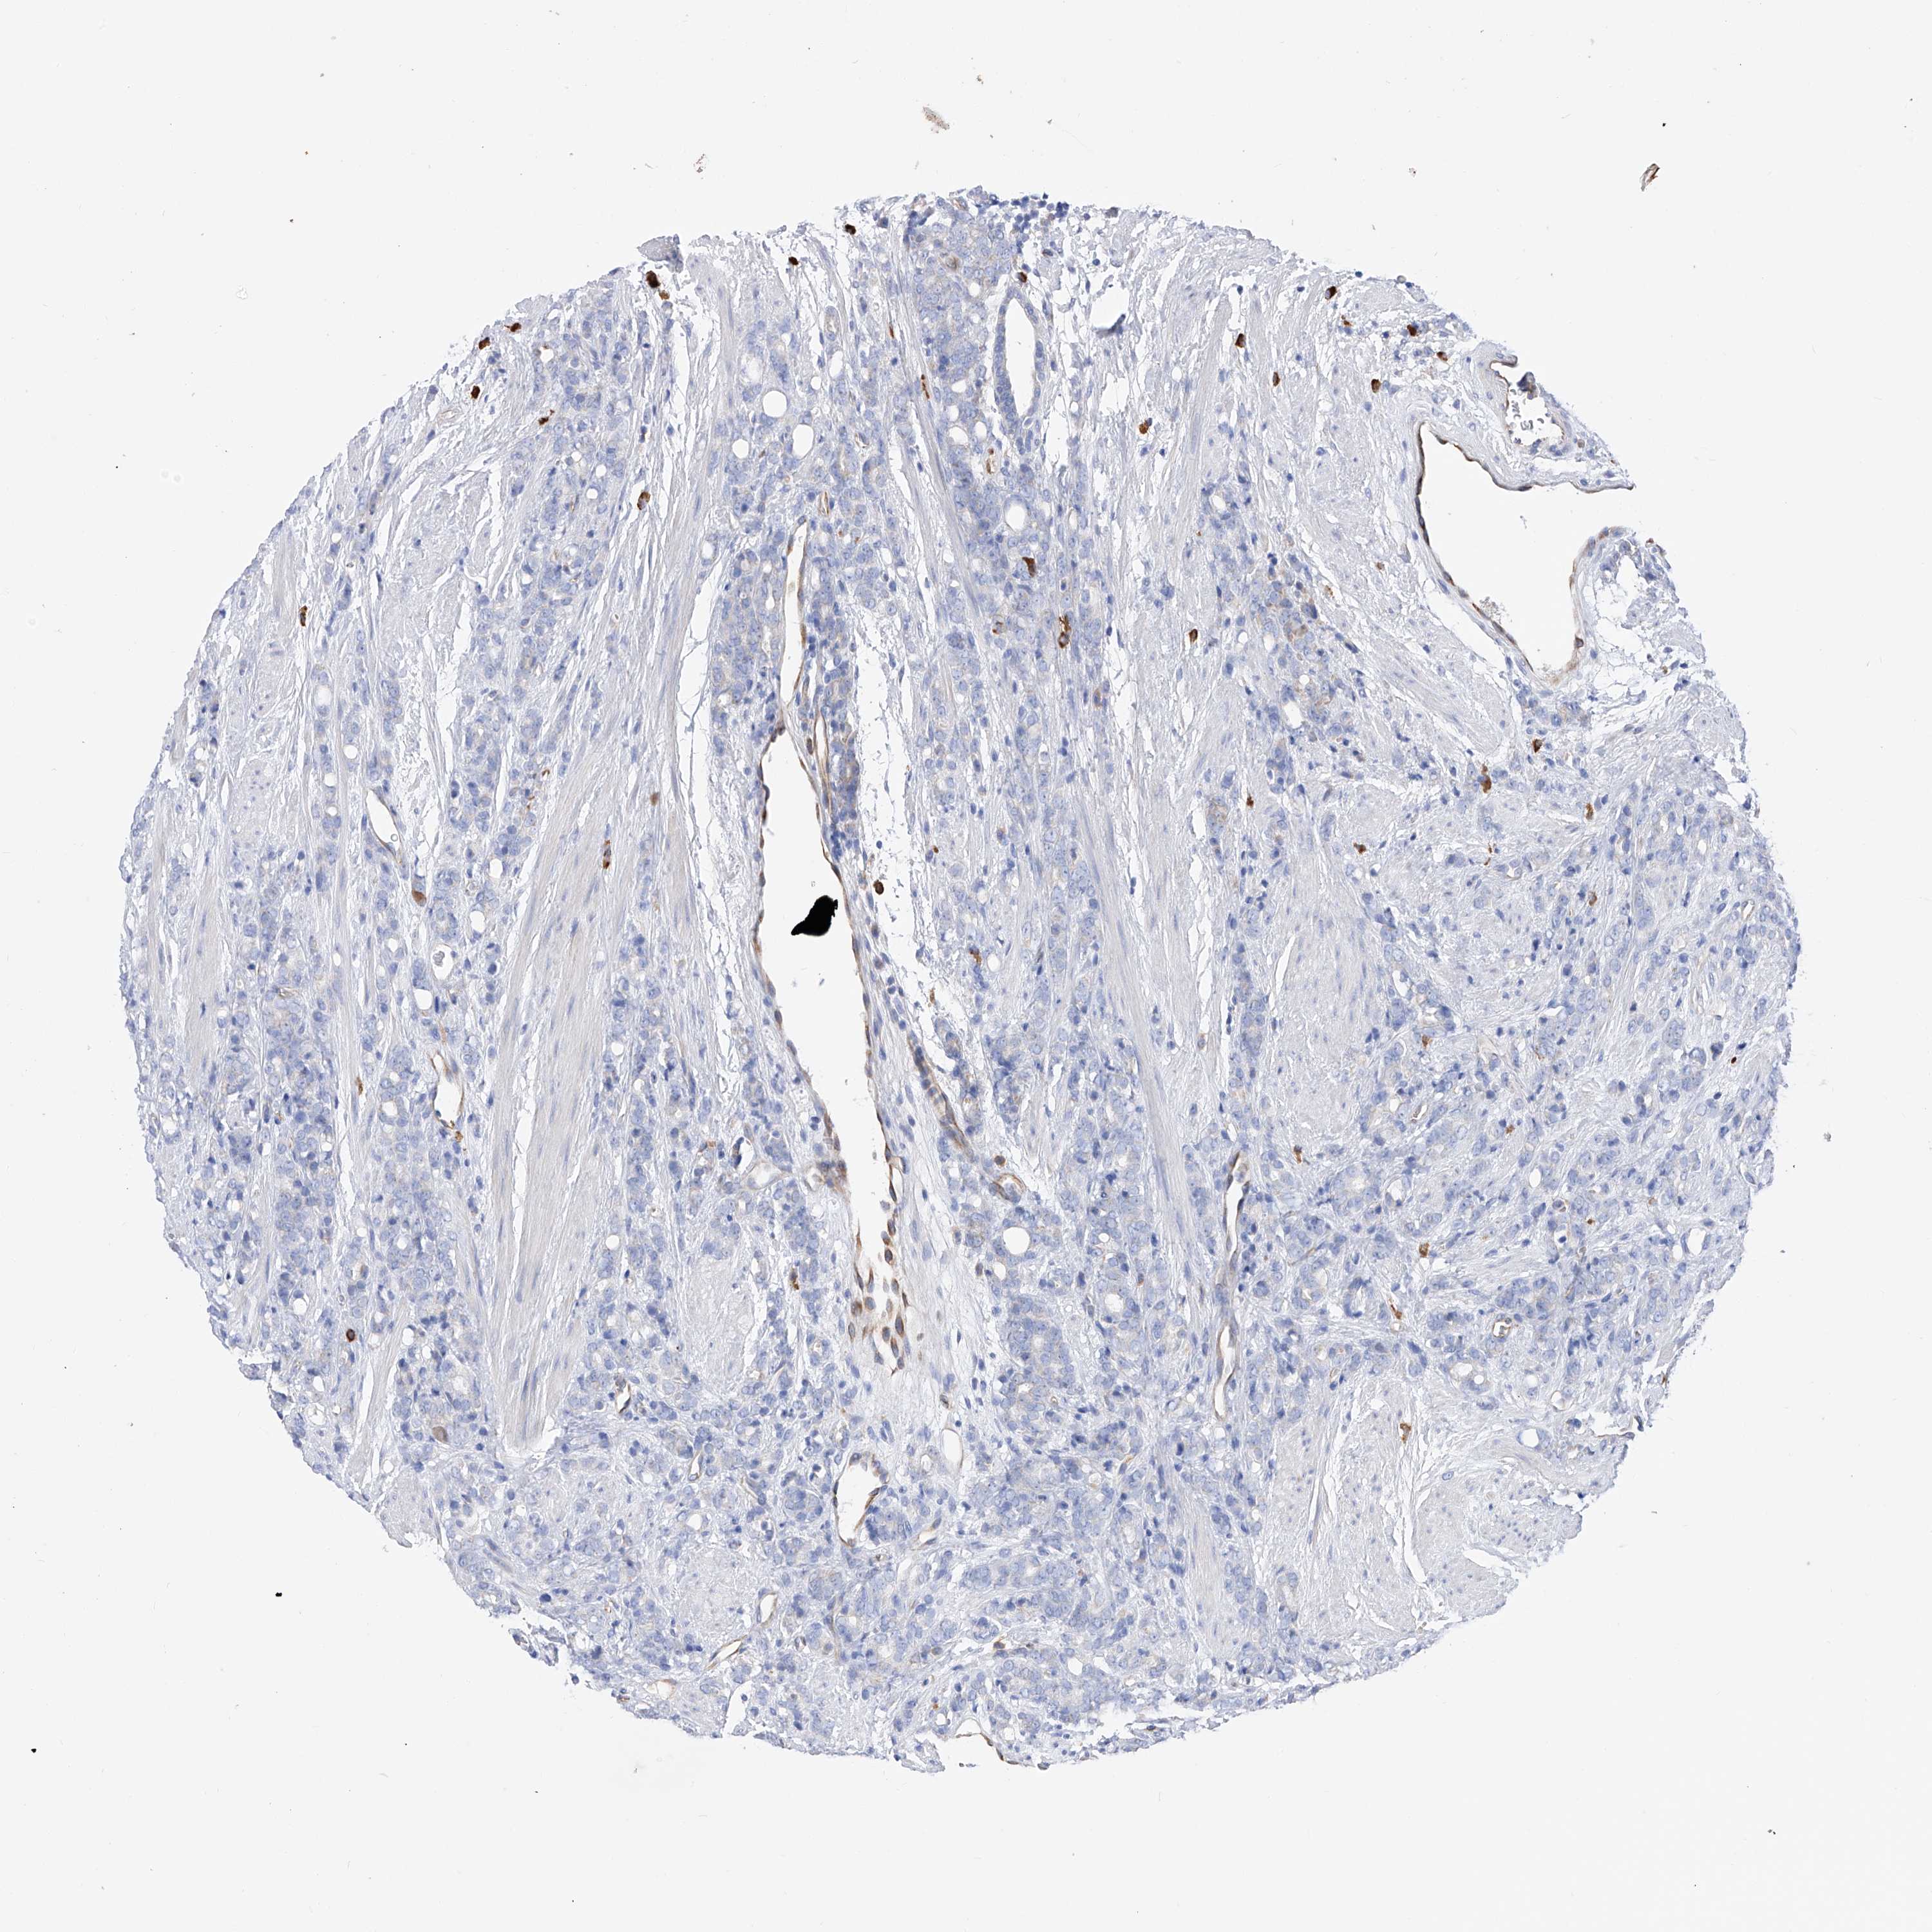

PROSTATE CANCER - Protein expressioni

A mouse-over function shows sample information and annotation data. Click on an image to view it in a full screen mode. Samples can be filtered based on level of antibody staining by selecting one or several of the following categories: high, medium, low and not detected. The assay and annotation is described here.

Note that samples used for immunohistochemistry by the Human Protein Atlas do not correspond to samples in the TCGA dataset.

Antibody stainingi

Antibody staining in the annotated cell types in the current human tissue is reported as not detected, low, medium, or high, based on conventional immunohistochemistry profiling in selected tissues. This score is based on the combination of the staining intensity and fraction of stained cells.

Each image is clickable and will lead to virtual microscopy that enables deeper exploration of all samples and also displays staining intensity scores, fraction scores and subcellular localization as well as patient and tissue information for each sample.

Antibody HPA030188

Antibody HPA030189

Antibody CAB002210

Staining

Adenocarcinoma, High grade

Adenocarcinoma, Low grade

Adenocarcinoma, Medium grade